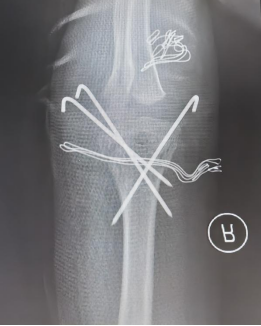

入院次日,在与家属充分沟通并取得同意后,医院紧急为患儿安排手术。手术台上,小儿骨科团队凭借丰富的临床经验和精湛的手术技术,成功为其实施“肱骨髁上骨折闭合复位+钢针内固定术”。该术式规避了传统切开手术的较大创伤,通过精准的透视引导与手法复位,使移位的骨折端实现满意对位,最大程度减少了对周围软组织及生长板的干扰,契合儿童骨折微创治疗原则。

小儿骨科团队进行术中闭合手法复位+经皮钛针固定

术后X线检查提示骨折复位效果佳

术后复查X线片显示,患儿骨折复位效果理想、对位对线良好,为患肘功能的顺利恢复筑牢基础。目前,在医护人员的专业指导与系统化康复计划的锻炼下,患儿正稳步恢复。家属对医院高效的救治流程、骨科团队高超的技术水平,以及全程温暖的医疗服务表达了由衷感谢。